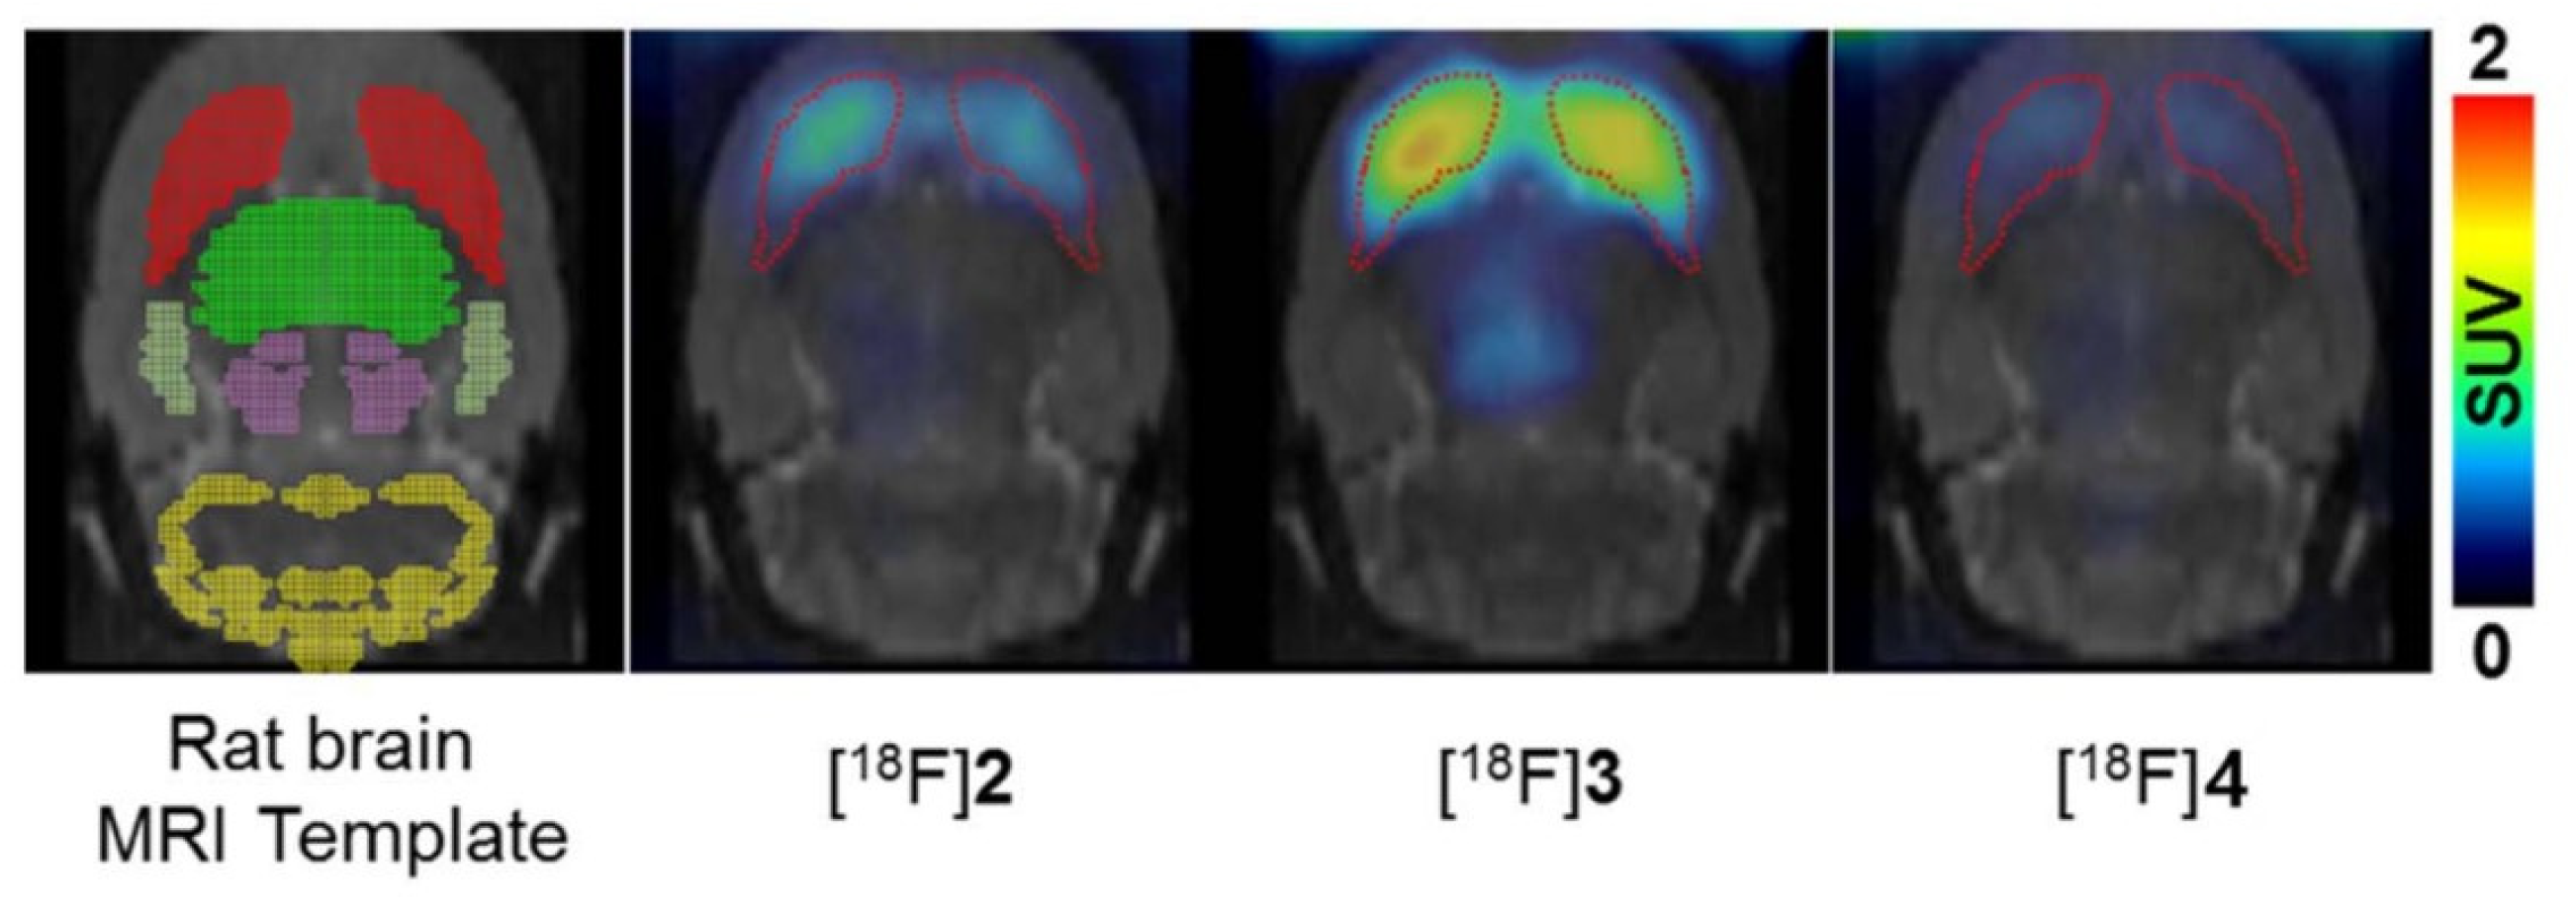

- Lee, B.C.; Moon, B.S.; Park, H.S.; Jung, J.H.; Park, D.D.; de Candia, M.; Denora, N.; Altomare, C.D.; Kim, S.E. The position of fluorine in CP-118,954 affects AChE inhibition potency and PET imaging quantification for AChE expression in the rat brain. European Journal of Pharmaceutical Sciences 2017, 109, 209-216. [CrossRef]